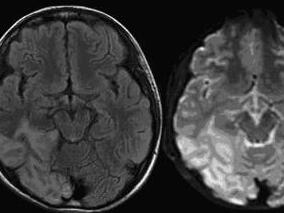

1小时条评论19岁男性,反复发作头痛伴抽搐,病程4年。病程初期反复发作头痛,无影像学改变。2年后头痛再次发作伴右侧偏盲,伴癫痫大发作,头颅MRI发现病灶,有枕叶癫痫反复发作;病后3年每隔10天发热头痛。病后4年头痛频繁,再次癫痫发作。该患者的诊断可谓一波三折。在该院最终...

1小时条评论线粒体脑肌病是由各种原因使线粒体DNA(mtDNA)和(或)核DNA(nDNA)发生基因突变,细胞内线粒体的结构与功能异常,导致细胞呼吸链及能量代谢障碍的一组疾病。由于对本病缺乏认识或因检查方法受限,常易误诊。下面这例病例,看专家如何慧眼识别该疾病。 临床资料 ...